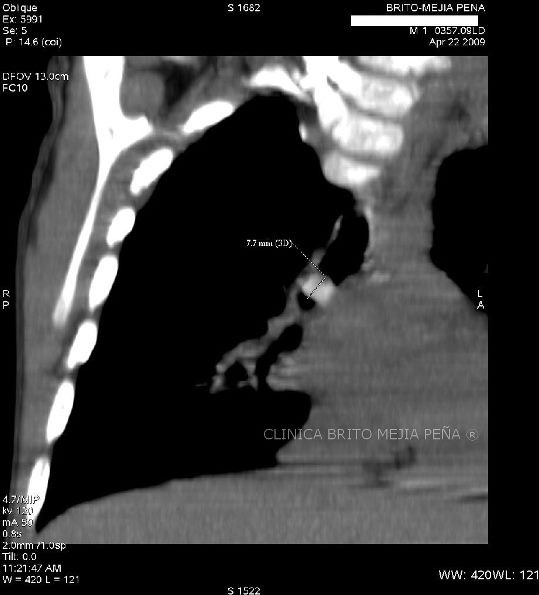

Cuerpo extraño en bronquio derecho